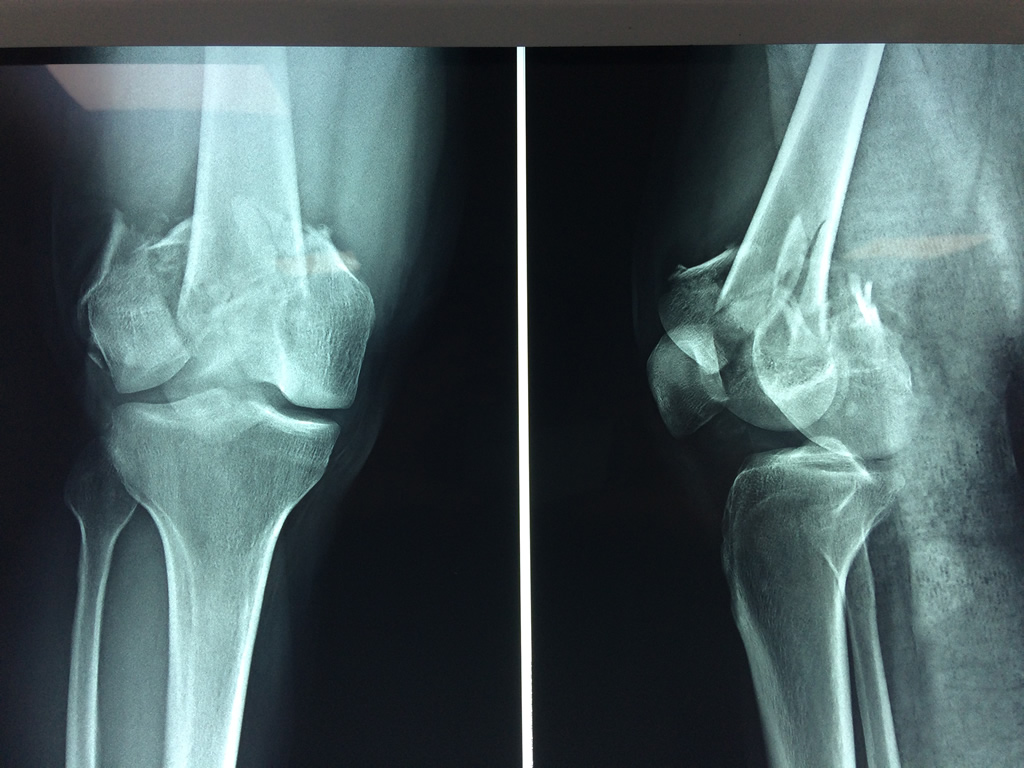

Cirugías de Cadera

El fémur es el hueso del muslo, el segundo segmento del miembro inferior. Es el hueso más largo, fuerte y voluminoso del cuerpo humano.